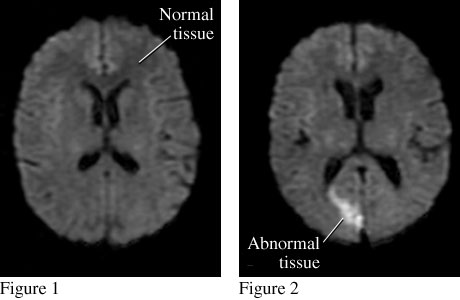

Figure 1 is a top view of the brain that shows normal tissue. Figure 2 is a similar view that shows abnormal tissue caused by a stroke.